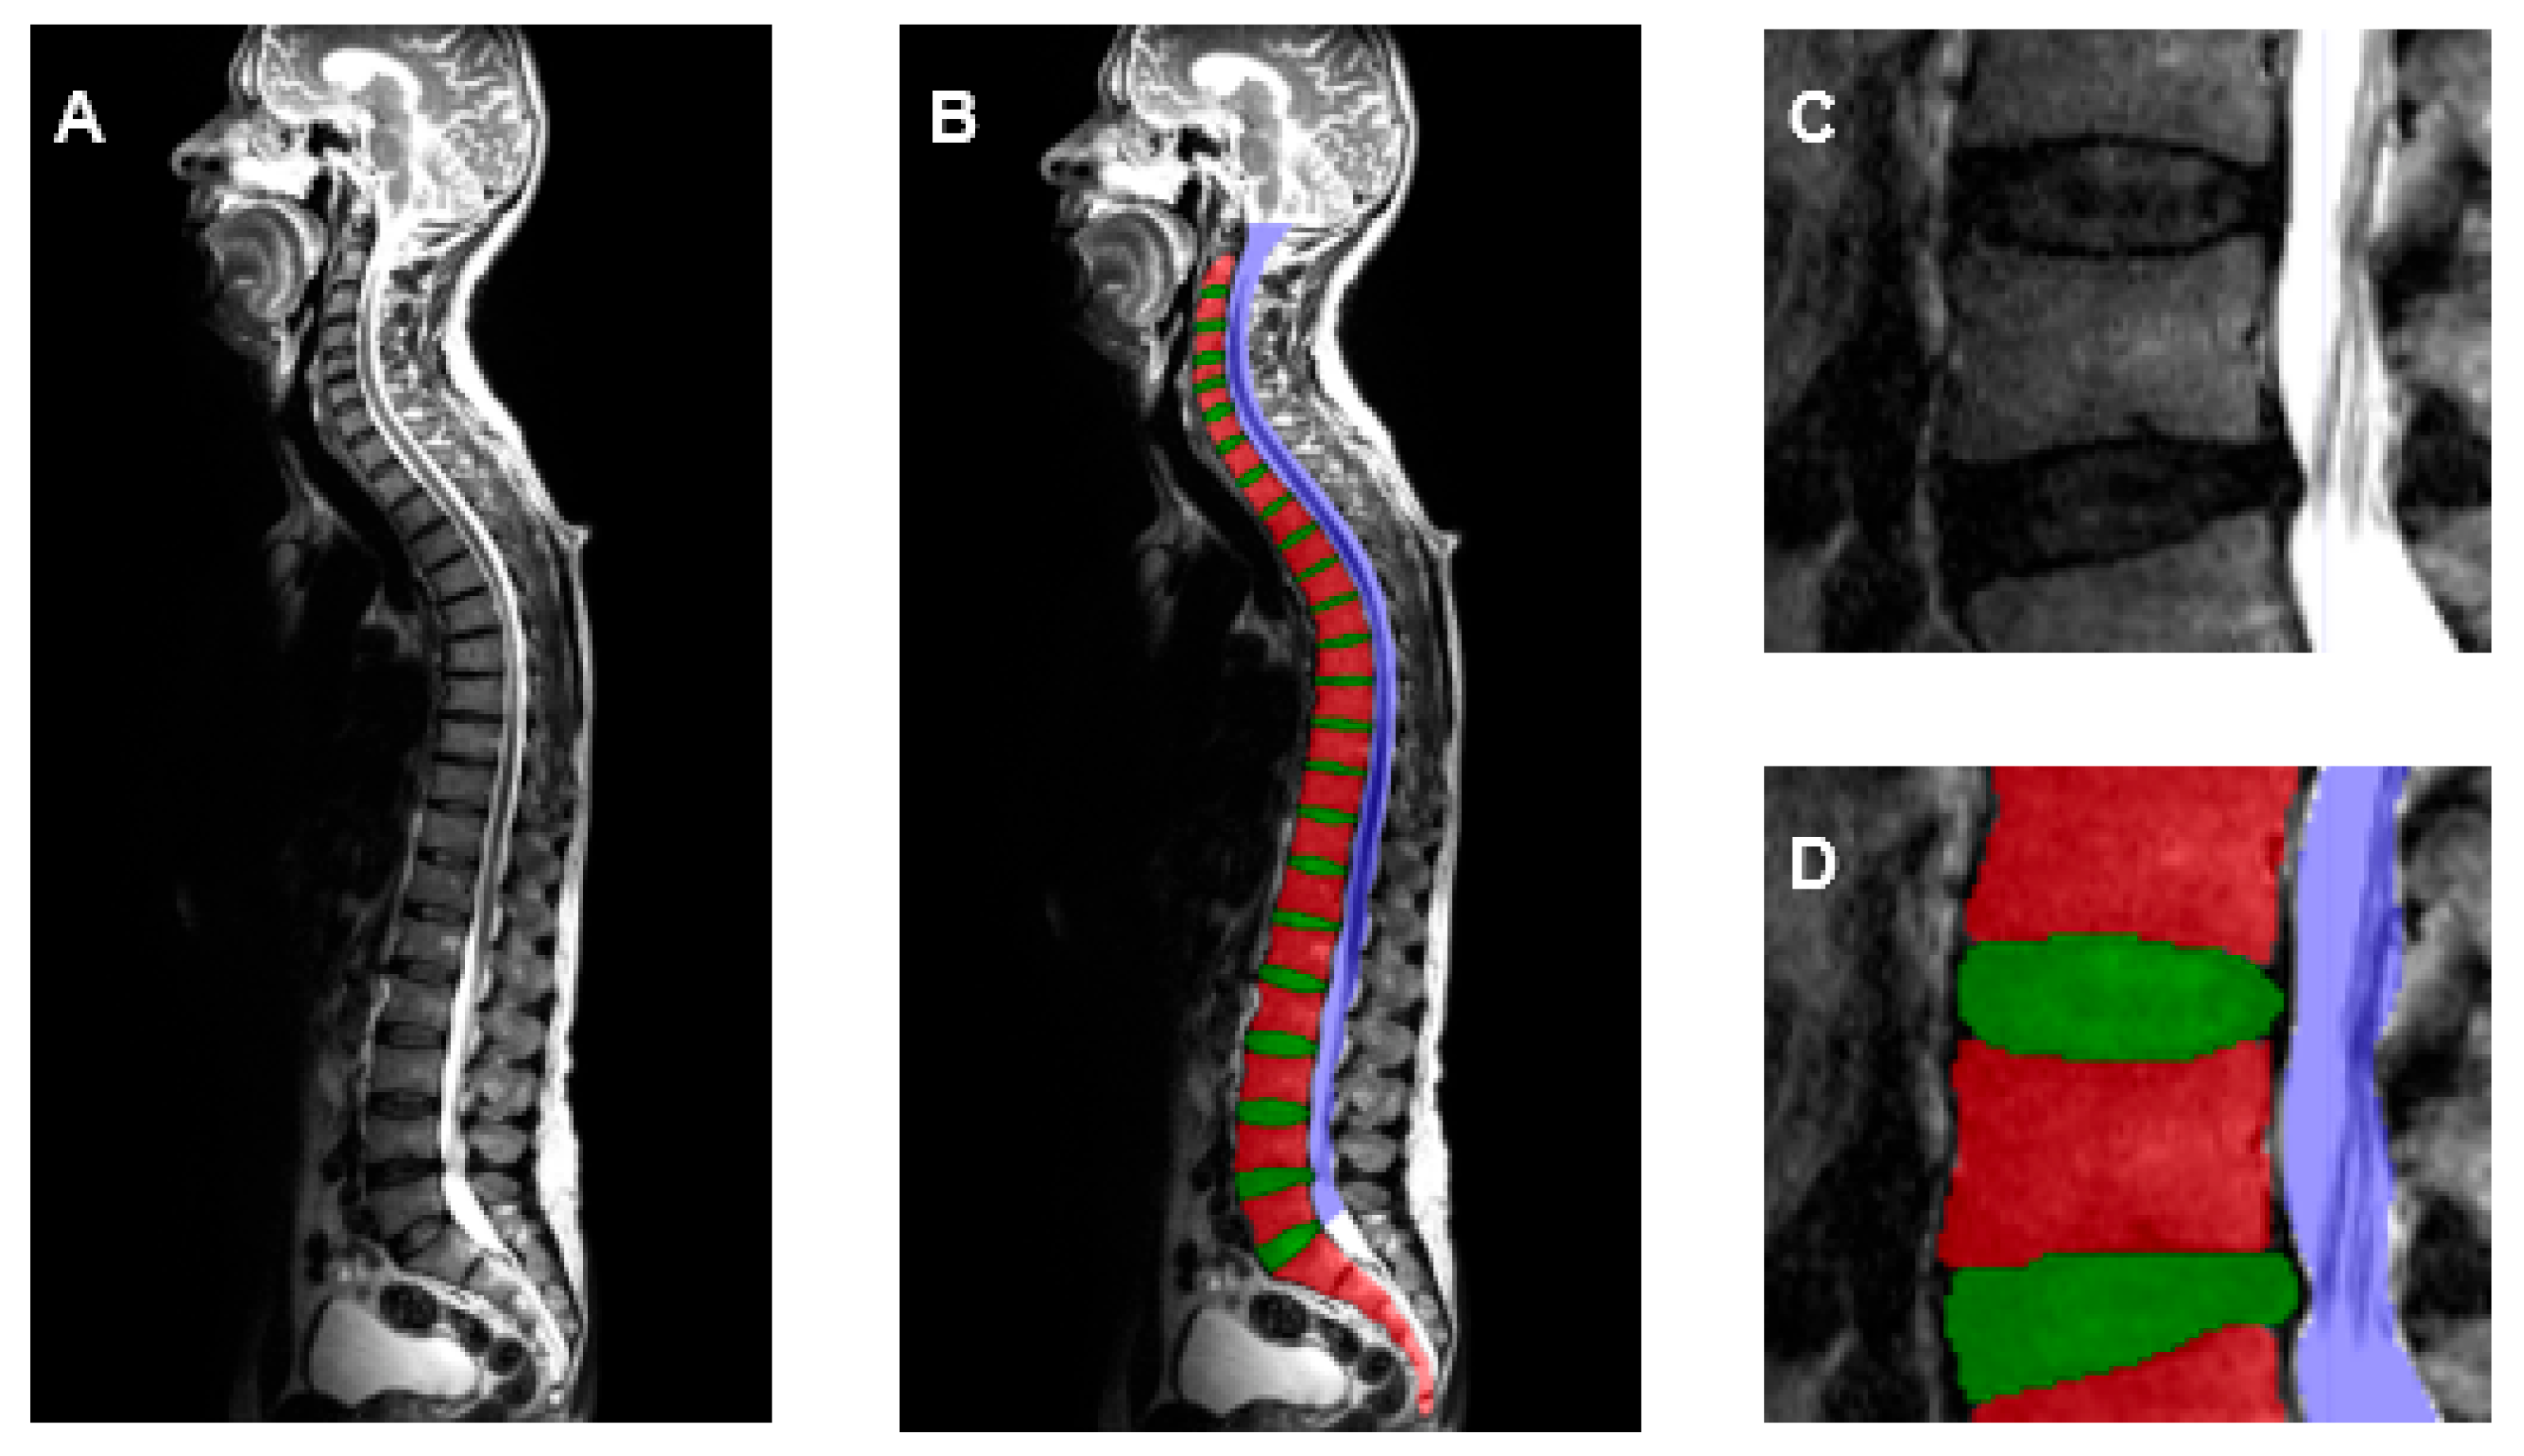

| VB | VD | SC | |

| Precision | 0.908 | 0.902 | 0.926 |

| Recall | 0.909 | 0.908 | 0.924 |

| Dice-score | 0.908 | 0.905 | 0.925 |